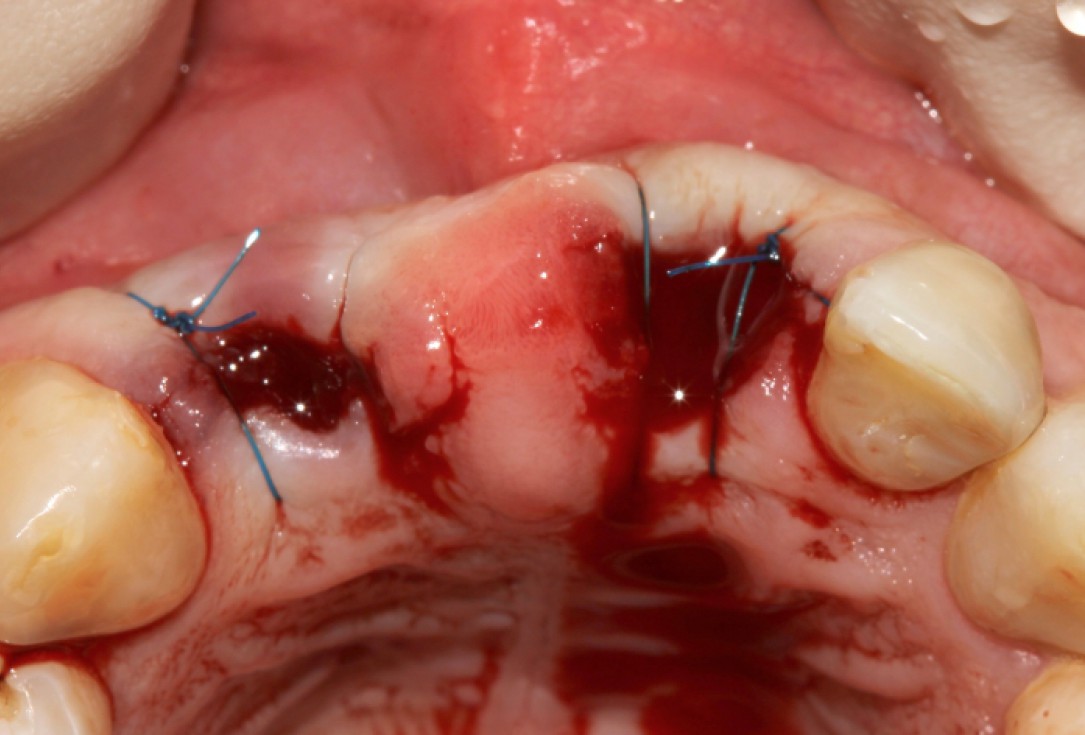

GBR and soft tissue augmentation with cerabone® and mucoderm® - H. Maghaireh & V. Ivancheva

Initial situation: missing teeth #11 & 12 and badly broken #21 root